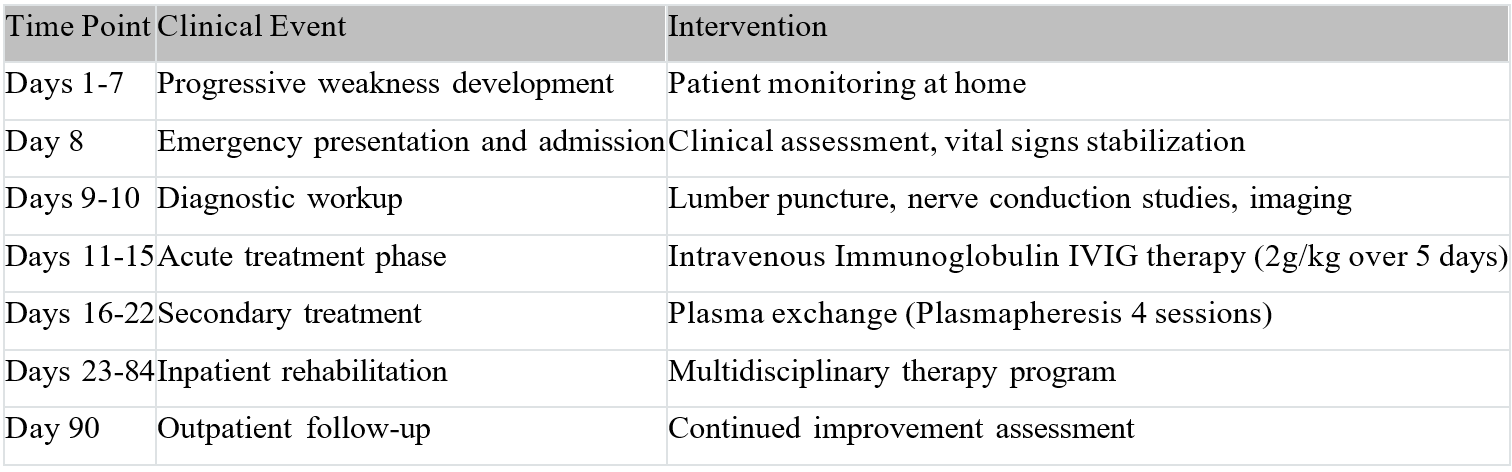

Imaging studies (Figures 1 and 2 as shown):

Figure 1: Cervical spine magnetic resonance imaging (MRI) revealed multilevel spondylosis with significant spinal canal stenosis and compression myelopathy at C4-C5 levels, showing hyperintense T2 signal changes indicating myelomalacia.

1. Cervical Myelopathy clinical considerations: initially suspected due to documented cervical spondylosis with compression at C4-C5 levels on MRI imaging [2,6].

This case illustrates the diagnostic complexity that arises when GBS presents concurrently with structural spinal pathology [2,6]. The presence of cervical spondylosis with compression myelopathy at C4-C5 levels initially complicated the clinical assessment, as both conditions can present with sensorimotor deficits.